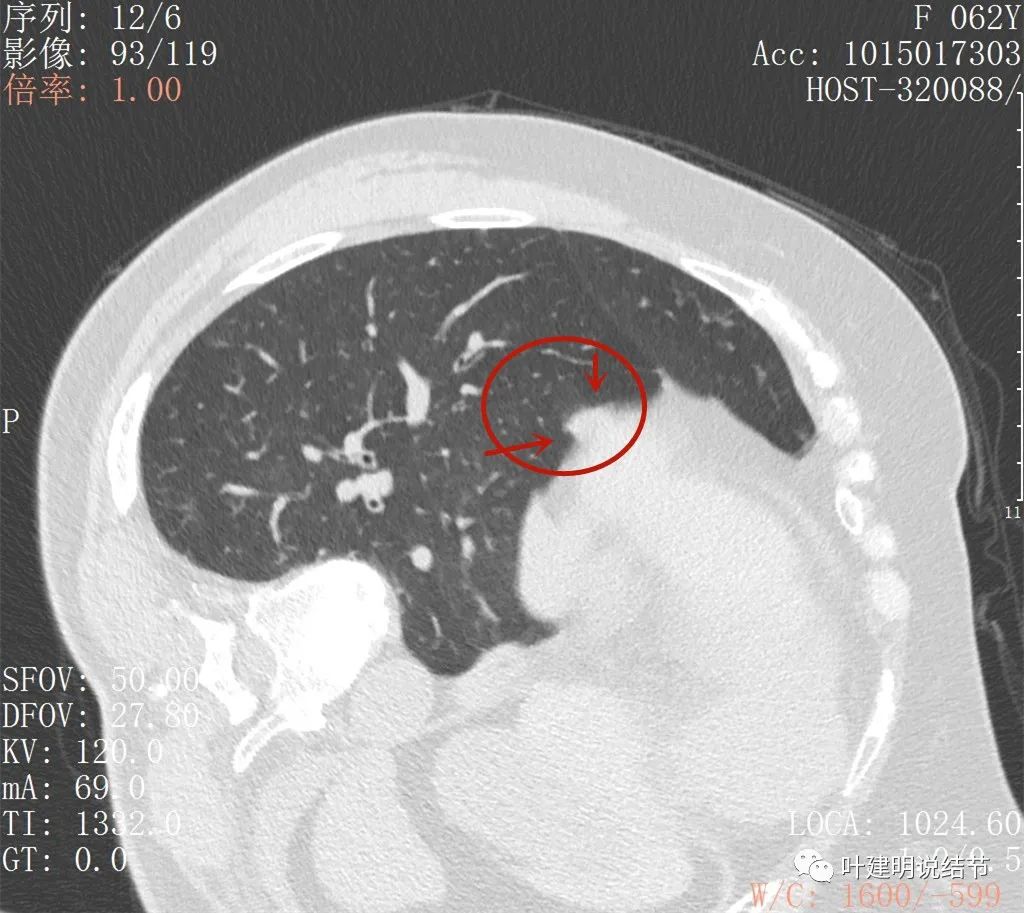

这是最近一次平扫的片子,此结节感觉有膨胀感,边界较清,位于肺底,贴膈面。我们从数次复查的对比,看来该结节是缓慢进展的,不吸收也不钙化,也不是纤维增生或条索状瘢痕的样子。在门诊我仔细对比了这些不同时间的片子后,认为右下这结节也极可能是恶性的,该干预。所以我们进一步查了靶扫描:

病灶出现,与膈肌间隙欠清

病灶呈实性密度,与膈肌间在此层面上看,并不侵犯或粘连,还是有缝隙的

上图粉色箭头示与膈肌间的缝隙,紫色箭头示病灶有细毛刺征,红色箭头示病灶实性密度